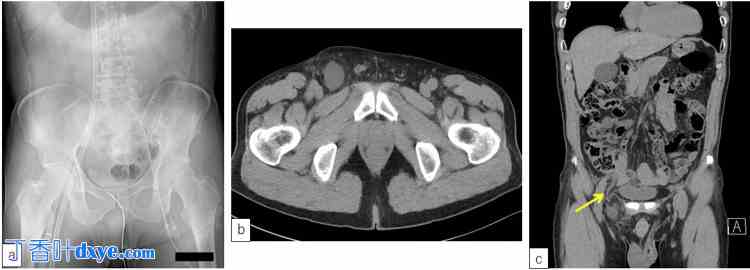

图1. VA-ECMO治疗期间腹部X光片和阑尾股疝腹部CT扫描。

a:经右股动脉插入VA-ECMO血液流入套管,经右股静脉插入血液流出套管,经左股动脉插入主动脉内球囊泵导管;b:尽管存在液体潴留,但未观察到穿孔迹象;c:在右股疝中观察到阑尾(箭头)。(b:轴向切面;c:冠状切面)。VA-ECMO:静脉-动脉体外膜肺氧合

入院时,患者无腹膜炎,疼痛局限于右腹股沟区。虽然患者无发热,血液检查结果也未显示炎症加重,但腹部CT扫描显示右股疝累及阑尾(图 1b、1c)。作者诊断为德·加伦格奥疝,并在征得患者同意后进行了腹腔镜手术。